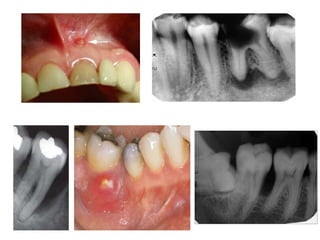

Management Of Enamel Defects A Case Report Of Identical Twins With Enamel Defects Of The Permanent Dentition Dental Update

Periodontal Pocket